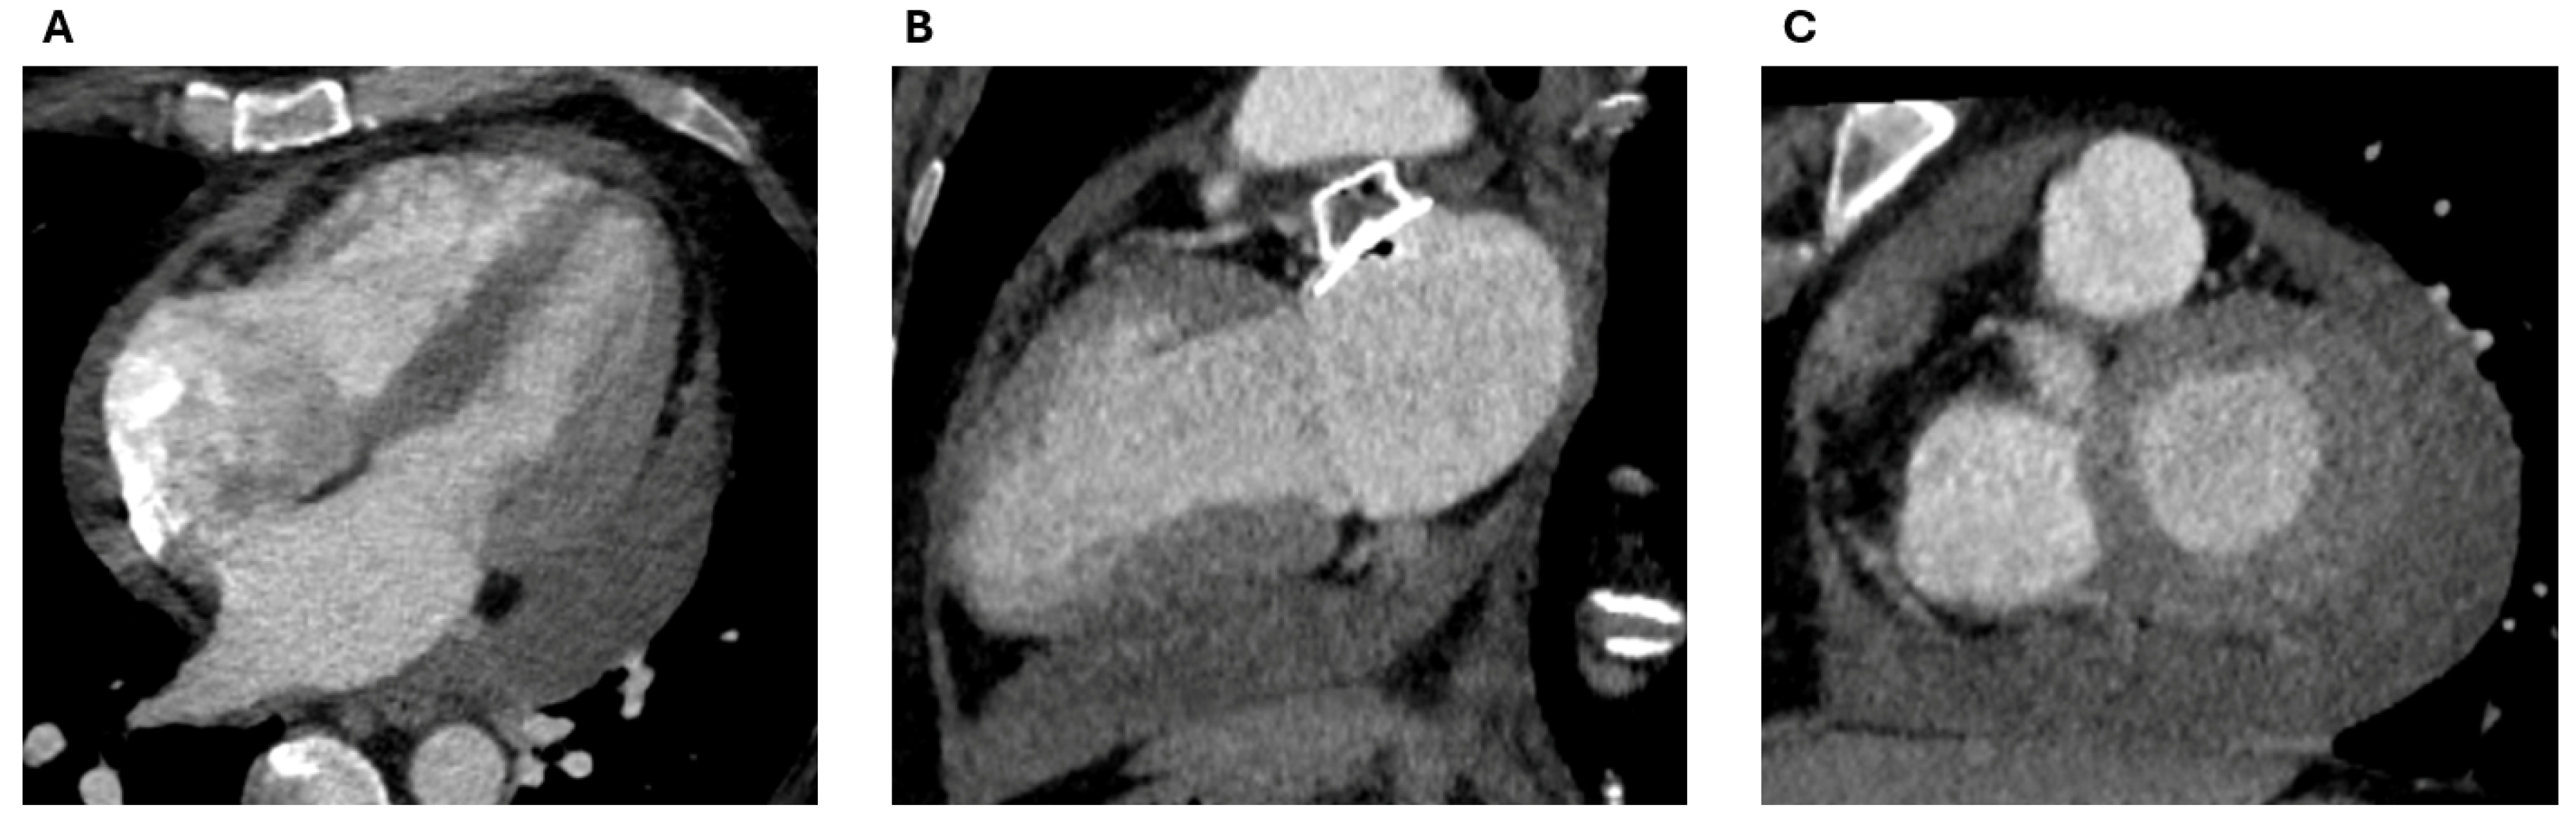

3.4. Pericardial Effusion and Device Erosion

3.5. Epicardial Devices